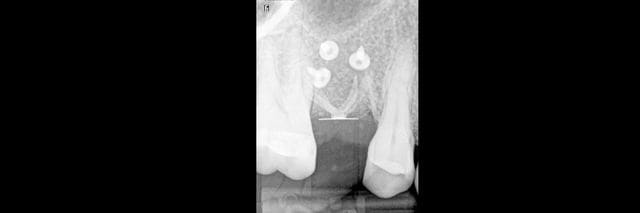

Bon ben voilà j'ai réalisé une ROG avec une membrane PTFE armé titane.

bien sûr les photos sont dans le désordre encore une fois ;)